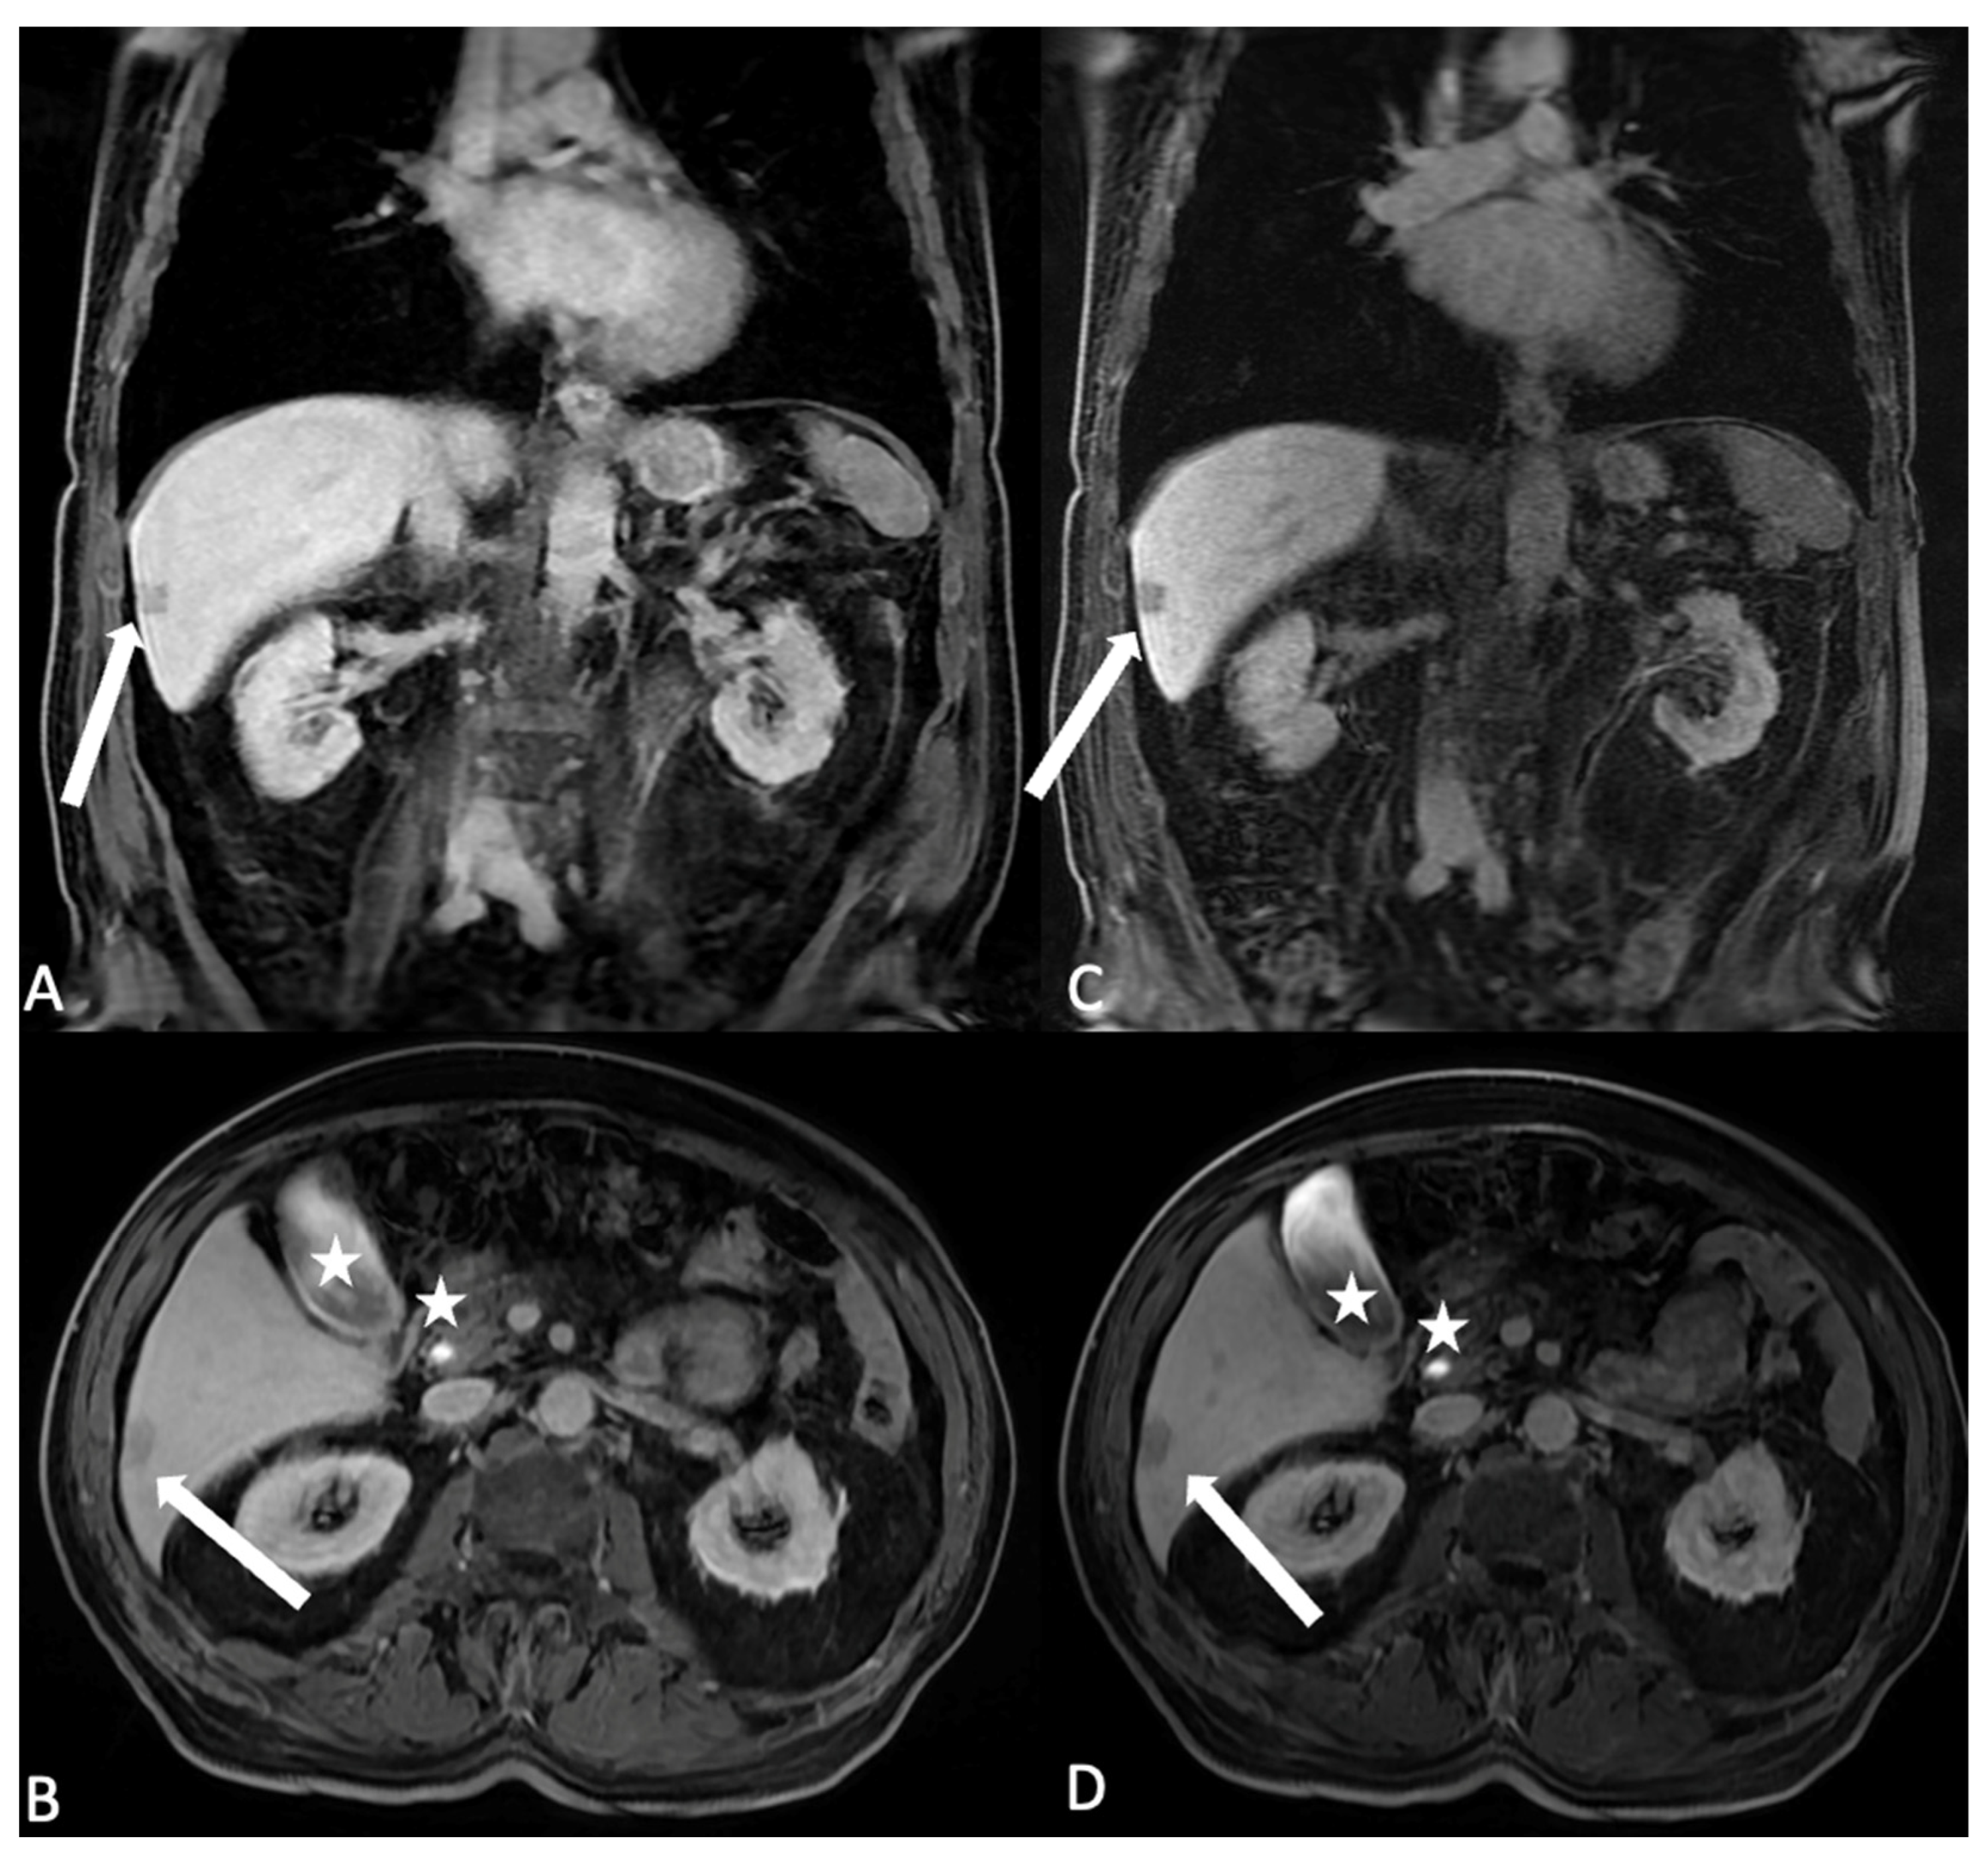

Figure 6. Axial and coronal T1 LAVA images after HSCA intravenous administration (gadobenate dimeglumine) of the same patient in hepatobiliary phase with different flip angle (FA) settings. (A,B) The FA is settled at 10 degree: the liver parenchyma results in the hepatobiliary excretion phase, and it is possible to identify the lesion with no hepatocyte uptake as hypointense (arrow), (C,D) changing the FA to 30 degree the hypointensity of the non hepatocitary lesion is better visible and identification is easier (arrow); moreover, the biliary signal results in better appreciated hyperintense signal (stars). Please note in the image, with the FA settled to 30 degree, the noise of the images increases; the modified flip angle is planned just in the last phases of acquisition.